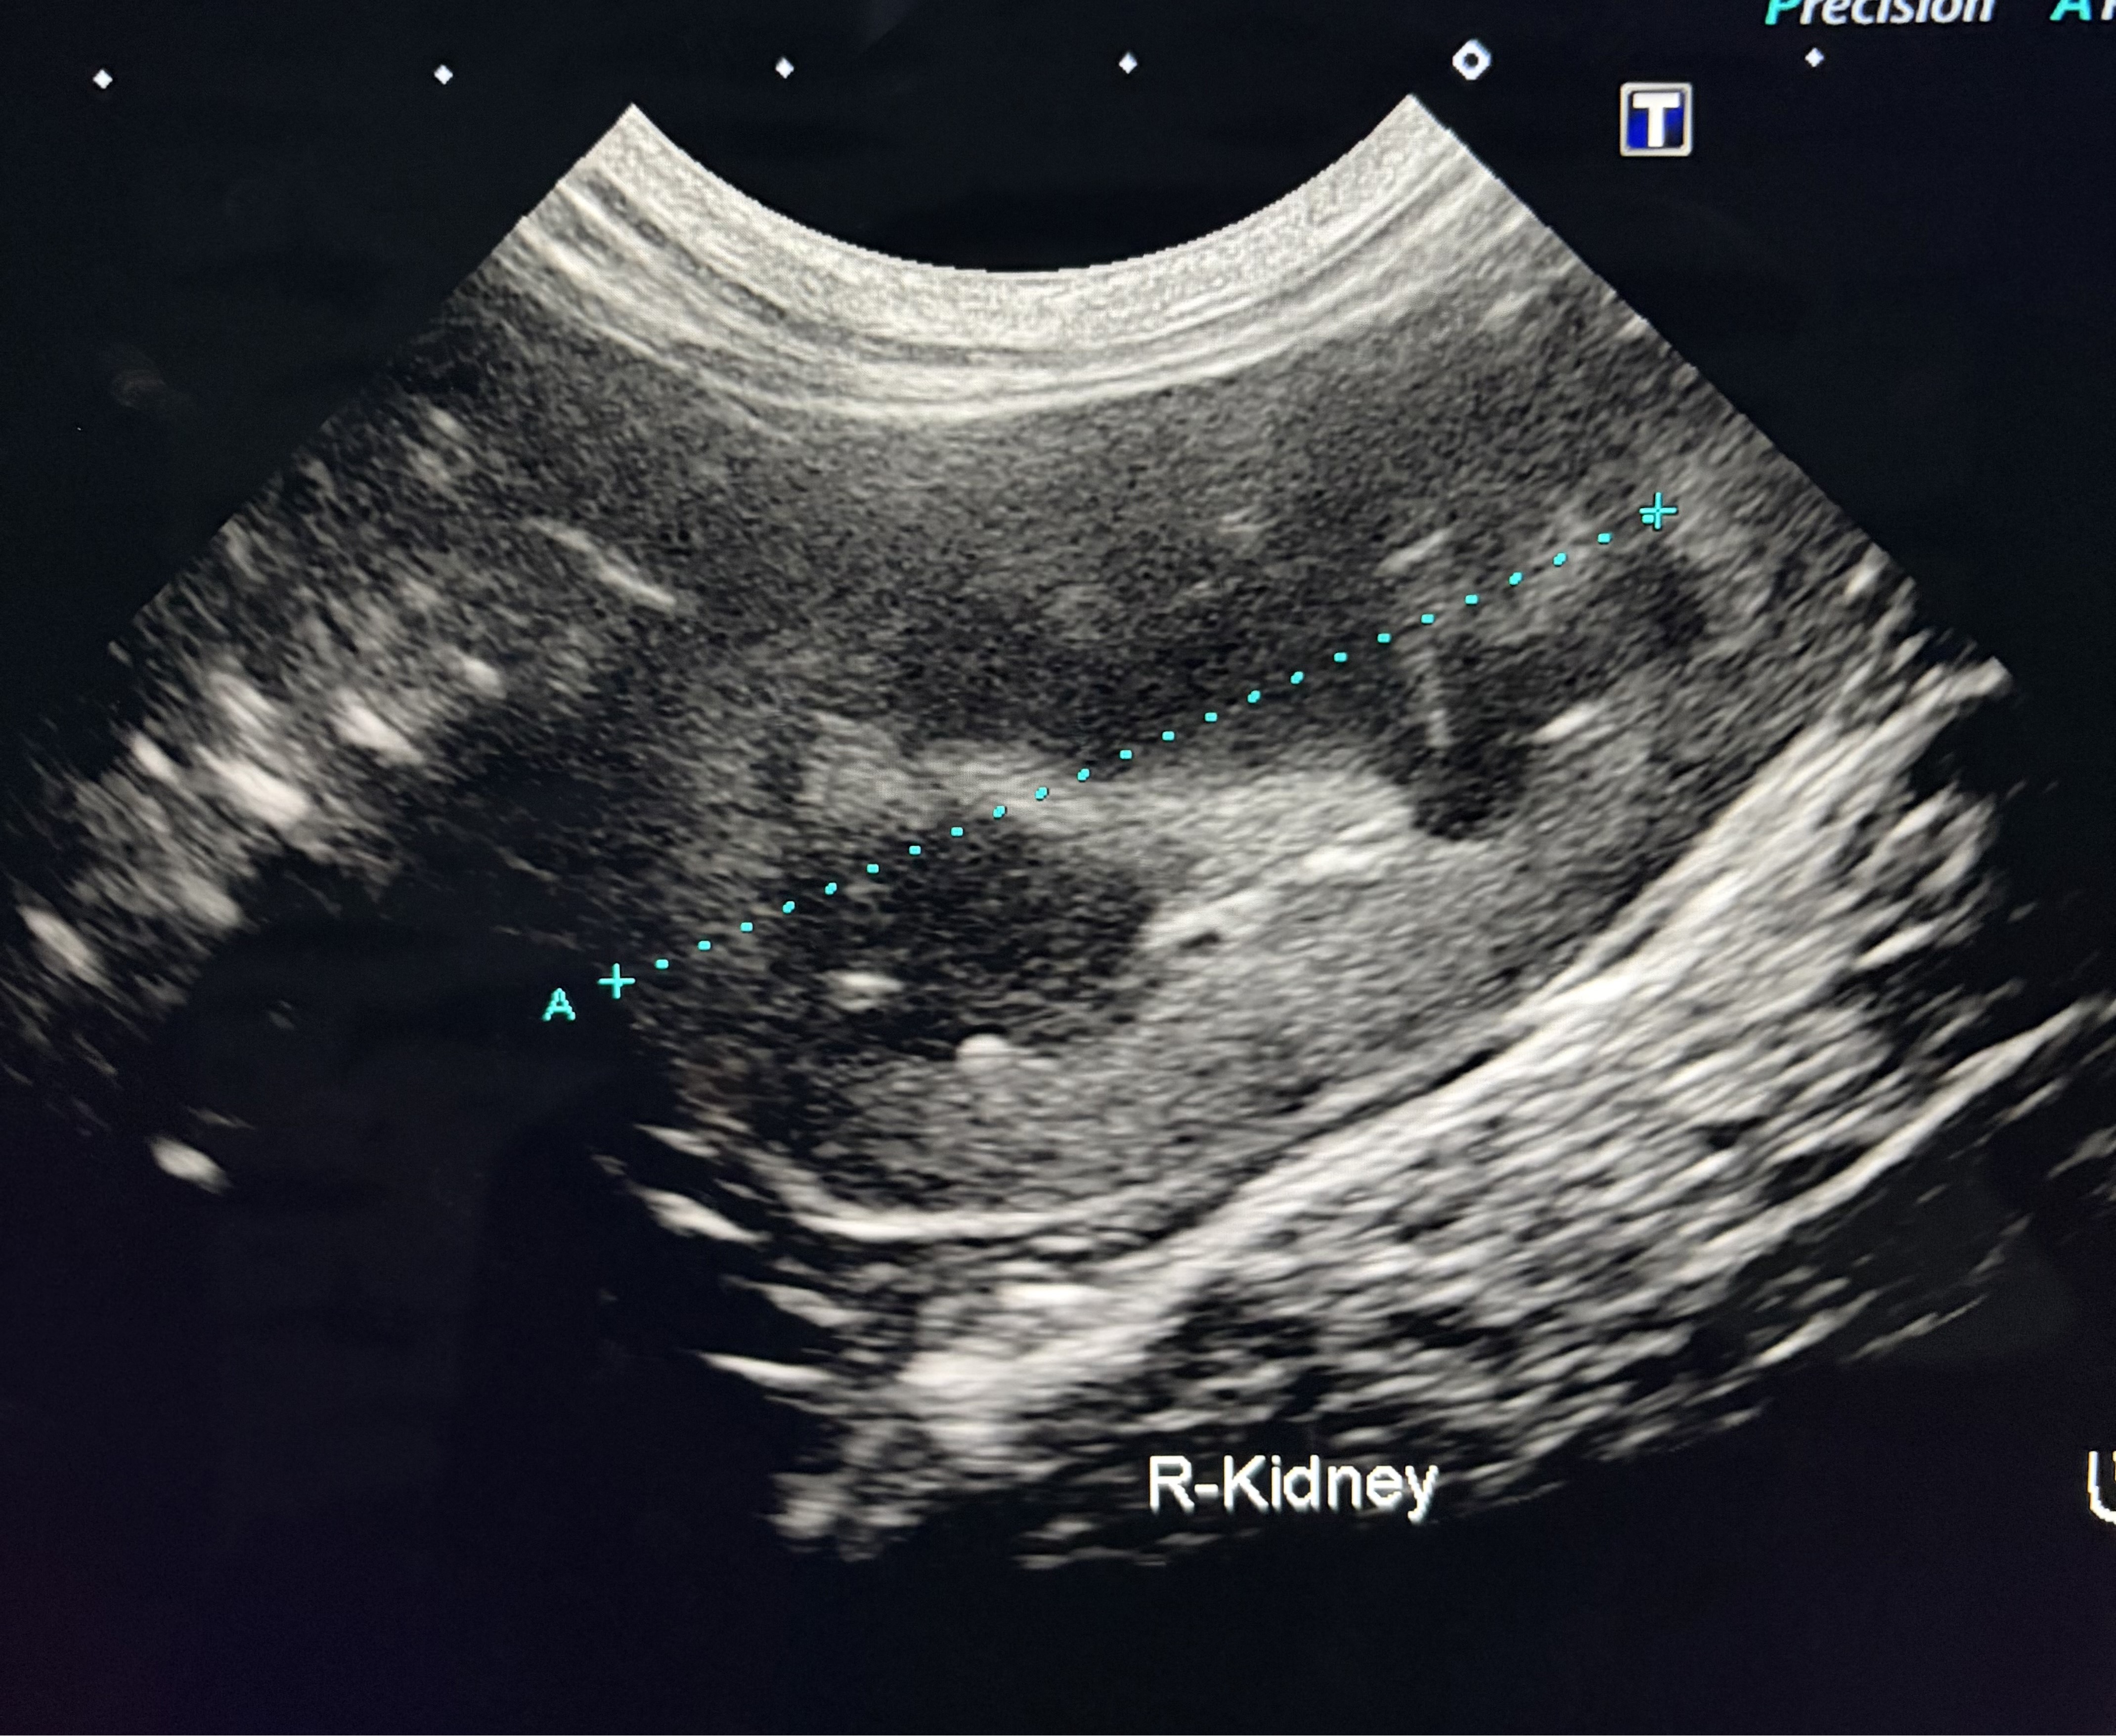

画像は潤ちゃんの腎臓のエコーの画像です。(左が右側、右が左側の腎臓です)

琥珀くんは身体的に特に問題はなかったですが、潤ちゃんは子猫の時の避妊手術の際に片方の子宮がなかったので、手術が終わってから腹部のエコー検査をした所、左側の腎臓が通常より小さかったです。

琥珀くんと潤ちゃんは、現在、半年に一度の血液検査と、年に一度のレントゲン・腹部のエコーの画像検査と尿検査をしています。